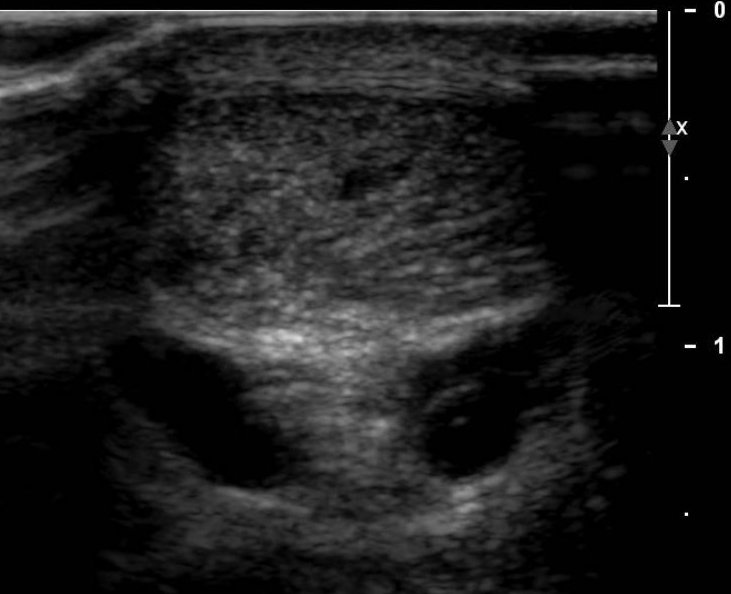

Nous gradons les synovites des arthrites inflammatoires par un score échodoppler (main/pied). Il est maintenant possible dans la plupart des cas de confirmer par échographie la présence d'un tunnel carpien et dans le même temps de rechercher les variantes de la normale qui pourraient compliquer une éventuelle opération.